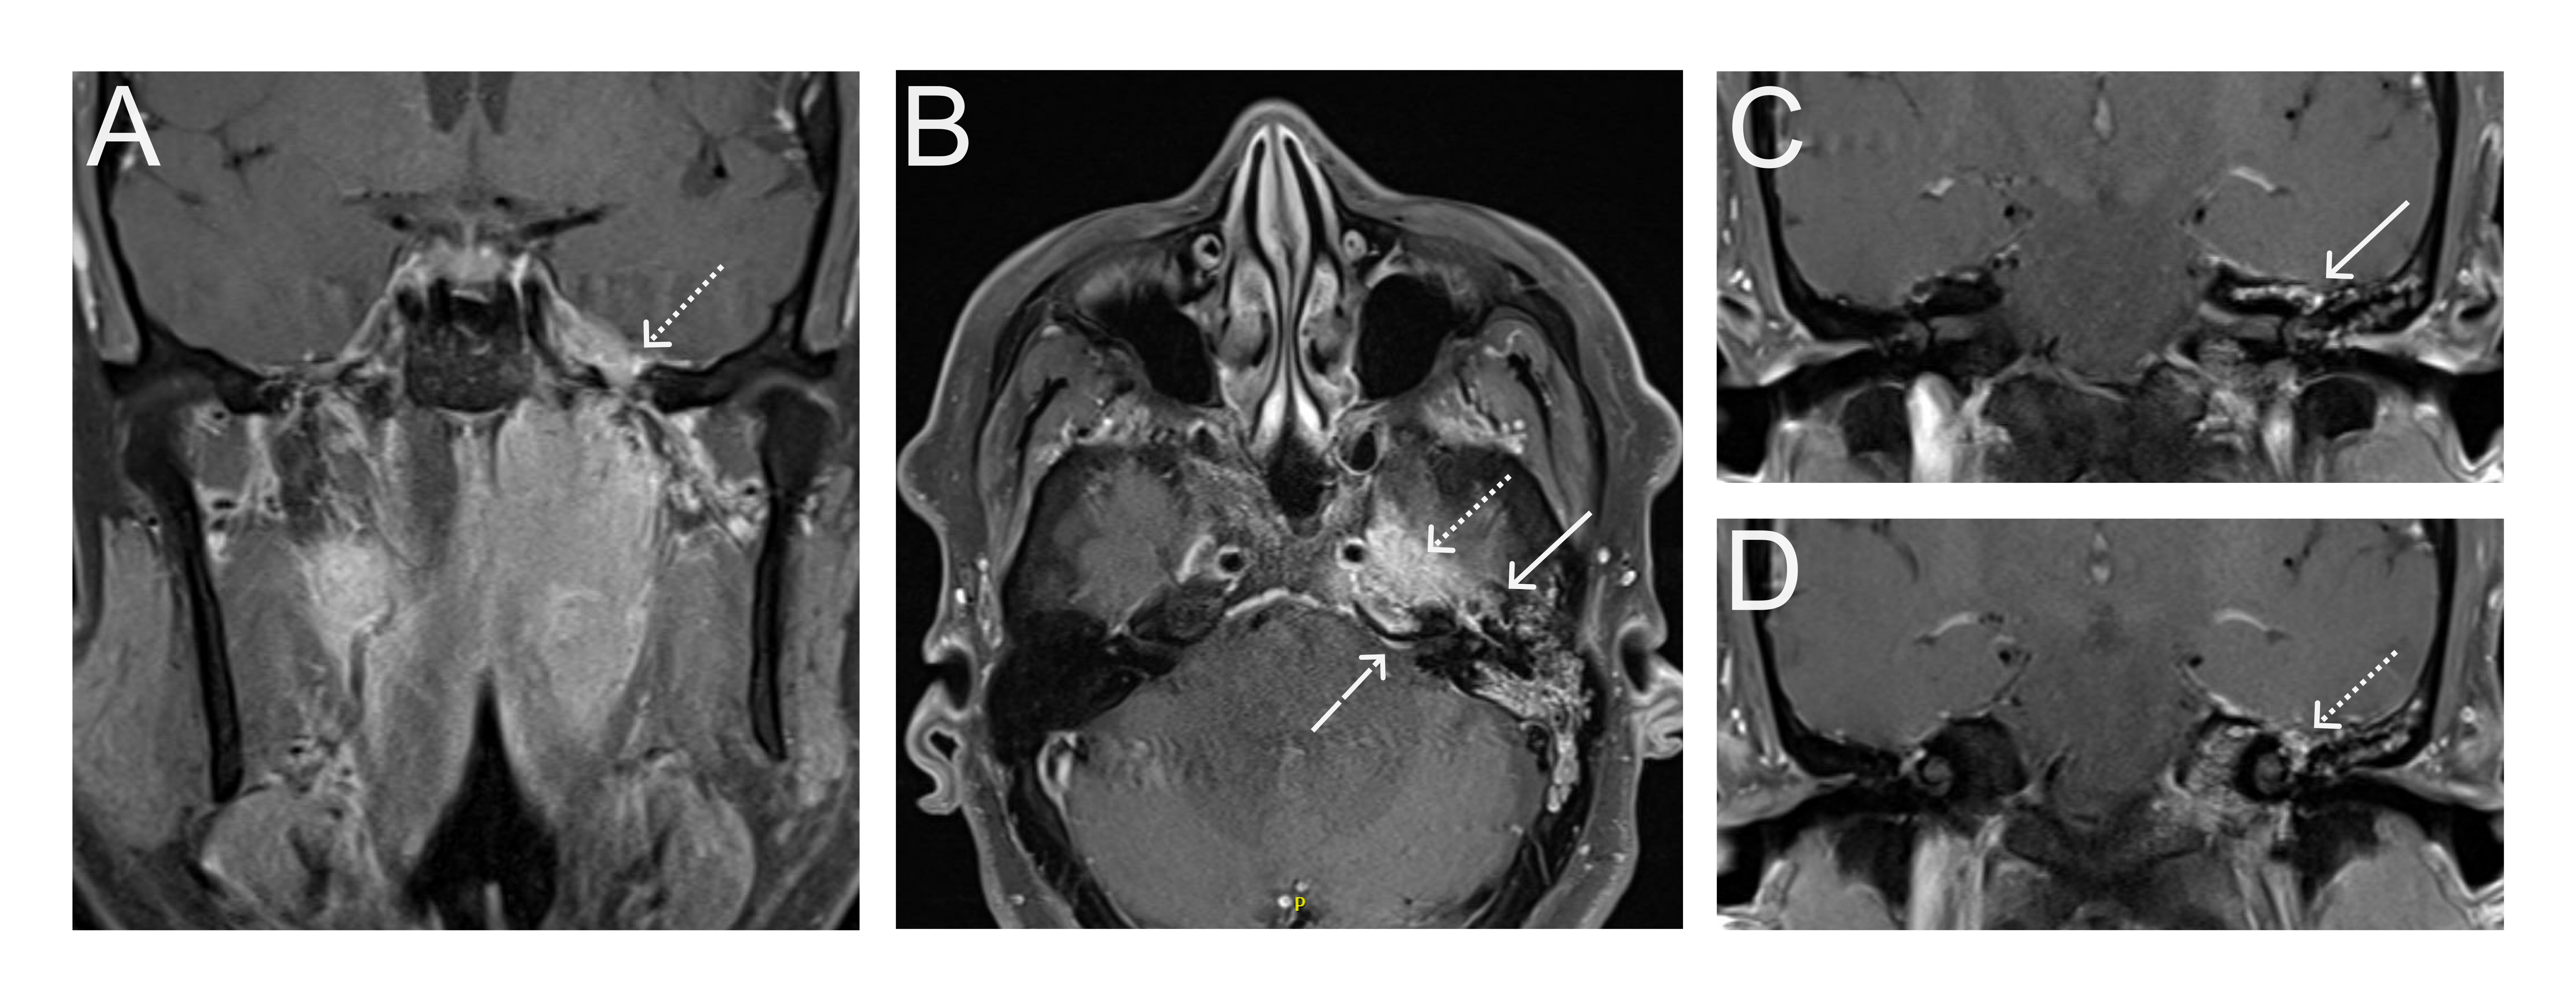

A 67-year old woman with chronic hypertension, hyperlipidemia and diabetes mellitus non-compliant to medication presented with a 10-day history of recurrent visual phenomena in the left visual field. She described stationery multi-coloured flashing lights which decreased in intensity, brightness and size after 3 minutes. She was alert and conscious during attacks. There was no limb jerking. Neurological examination was normal with no visual field defect. Capillary glucose was 28.1 mmol/L, Hba1c 9% and B-hydroxybutyrate < 0.1. She was treated with actrapid 8 units, glipizide 5 mg BD and empagliflozin 12.5 mg OM. Interictal electroencephalogram was normal with no epileptiform activity. Brain magnetic resonance imaging revealed restricted diffusion in the right occipital cortex with corresponding cortical thickening and increased FLAIR signal with subtle hypodensity on GRE sequence. Her visual symptoms improved dramatically with hydration and diabetic control. She was treated with a short course of keppra. One month later repeat MRI brain showed resolution of the DWI and FLAIR abnormalities.

Initial dwi

D